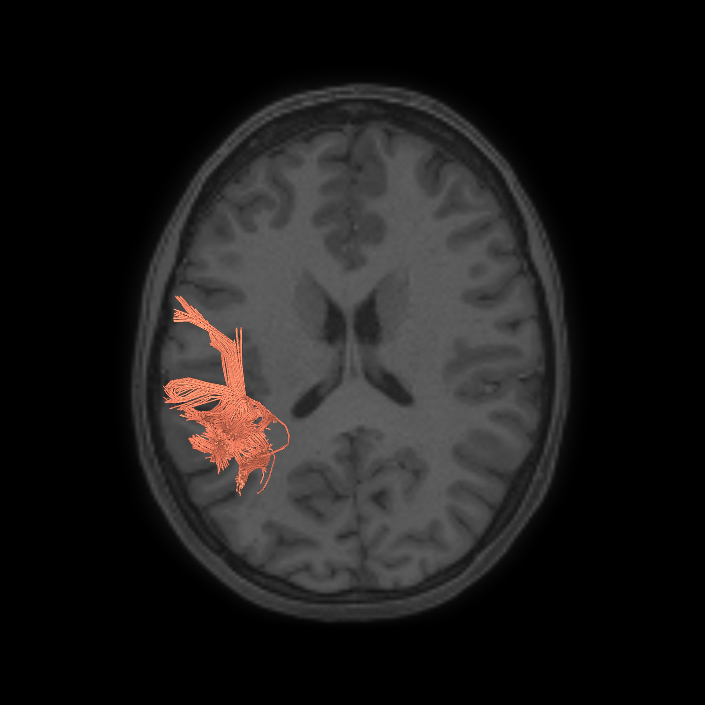

ᐅ SummaryArea 44: part of the inferior frontal gyrus of the lateral frontal lobe. Translates abstract and intentional information in the prefrontal cortex to more detailed representations to help guide the production of verbal and manual actions. In addition to its known association with Broca's area, is sometimes represented as part of Broca's complex ᐅ Where is it?Area 44 is at the posterior most part of the inferior frontal gyrus. It is the anterior bank of pars opercularis of the IFG. ᐅ What are its borders?Area 44 borders area 45 anteriorly and area 6r posteriorly. Area 8C is its medial border and its inferior border is wedged between then upper borders of Areas 6R and 6V. Its superior edge borders IFSp and IFJa. Its opercular surface is FOP4. ᐅ What are its functional connections?Area 44 demonstrates functional connectivity to areas SFL, IFSp, IFJa, 45, 47s, 47L, 9a, 9m, 8AV, 8BL and 8C in the dorsolateral frontal lobe, area 8BM in the medial frontal lobe, area 55b in the premotor areas, areas FOP5, AVI and PSL in the insula- opercular region, areas TGd, STSdp and STSvp in the temporal lobe, areas PFm, and PGi in the inferior parietal lobe, and no areas in the medial parietal lobe. ᐅ What are its white matter connections?Area 44 is structurally connected to the arcuate/SLF and the FAT. Connections with the arcuate/SLF project posteriorly and wrap around the Sylvian fissure to the middle temporal gyrus to end at TE1a and TE1m. There are also projections from the arcuate/SLF before it terminates to parcellations A5 and STSdp. The majority of the inferior connections of the frontal aslant tract end at 44, the tract is connected superiorly to superior frontal gyrus parcellations SFL, 6ma and s6-8. Local short association bundles are connected with 45 and 8C. White matter tracts from 44 in the right hemisphere have less consistent connections with the arcuate/SLF. ᐅ What is known about its function?Area 44 translates abstract and intentional information in the prefrontal cortex to more detailed representations to help guide the production of verbal and manual actions. Area 44, in addition to its known association with Broca's area, is sometimes represented as part of "Broca's complex", including Brodmann Areas 45, 46, 47 and the mesial supplementary motor area of 6, which contribute to a frontal-subcortical circuit. The right pars opercularis has also been implicated in cognitive inhibition in the overall context of working memory. |

DTI image |

ᐅ SummaryArea 45: part of the inferior frontal gyrus of the lateral frontal lobe. In addition to its known association with Broca's area, is sometimes represented as part of Broca's complex ᐅ Where is it?Area 45 is the lateral surface of pars triangularis of the IFG. ᐅ What are its borders?Area 45 borders area 47L anteriorly and area 44 posteriorly. Its superior edge borders area p47r, IFSa, and IFSp. Its opercular surface is conveniently named FOP5 ᐅ What are its functional connections?Area 45 demonstrates functional connectivity to areas SFL, IFSp, 44, a47r, 47s, 47L, 9a, 9p, 9m, 8AV, and 8BL in the dorsolateral frontal lobe, area 8BM in the medial frontal lobe, area 55b in the premotor areas, areas FOP5, and PSL in the insula-opercular region, areas TGd, TGv, TE1a, STSva, STSdp and STSvp in the temporal lobe, area PGi in the inferior parietal lobe, and area 31pd in the medial parietal lobe. ᐅ What are its white matter connections?Area 45 is structurally connected to the arcuate/SLF and IFOF. However, arcuate/SLF connections are not consistent across individuals. Connections with the arcuate/SLF project posteriorly and wrap around the Sylvian fissure to the middle temporal gyrus to end at TE1p. There are also projections from the arcuate/SLF before it terminates to parcellations A4 and PBelt. IFOF connections travel from 45 through the extreme/external capsule and continue posteriorly through the temporal lobe to end at occipital lobe parcellations V1, V2, V3 and V4. Local short association bundles connect with 44 and FOP4. ᐅ What is known about its function?Area 45, in addition to its known association with Broca's area, is sometimes represented as part of "Broca's complex", including Brodmann Areas 45, 46, 47 and the mesial supplementary motor area of 6, which contribute to a frontal-subcortical circuit. |

DTI image |

ᐅ SummaryArea 55b: part of the premotor areas. Relatively uncharacterized regions. In 1956, one of the only studies to characterize this regions concluded that the area played a role in language processing. ᐅ Where is it?Area 55b is located on the anterior half of the precental gyrus, approximately half way down its length along the convexity, just inferior to FEF. It also forms the adjacent floor of the precentral sulci and straddles slightly onto the posterior edge of the middle frontal gyrus. ᐅ What are its borders?Area 55b borders area FEF superiorly and PEF and area 6v inferiorly. Area 4 is its posterior border and areas 8AV and 8C form its anterior border across the precentral sulcus. ᐅ What are its functional connections?Area 55b demonstrates functional connectivity to area 4 in the motor strip, areas SCEF and SFL in the premotor areas, areas IFSp, IFJa, 8AV, 44, 45, and 47L in the lateral frontal lobe, areas STSda and STSdp in the temporal lobe, areas PSL and STV in the posterior opercular cortices, and area TPOJ1 in the lateral occipital lobe. ᐅ What are its white matter connections?Area 55b is structurally connected to the contralateral hemisphere and the superior longitudinal fasciculus. Contralateral connections course through the body of the corpus callosum to 6ma, 6a and 6mp. Connections with the superior longitudinal fasciculus connect 55b to parcellations PHT and PFm, and this tract terminates eventually in the temporal lobe at TGd. Local short association fibers connect with 8Av, 8C, IFJp, 3a, 3b and PEF. ᐅ What is known about its function?Area 55b is a relatively uncharacterized region. In 1956, one of the only studies to characterize this region concluded that the area played a role in language processing. |

DTI image |

ᐅ SummaryArea IFJa (inferior frontal junction, anterior): part of the lateral frontal lobe. Areas in the midventrolateral prefrontal cortex interact with posterior areas of the brain to retrieve specific auditory memories. The inferior frontal junction, in particular, serves as an important crossroads between bottom-up and top-down processing in the lateral prefrontal cortex. ᐅ Where is it?Area IFJA is located in the posterior portion of the inferior frontal sulcus. It comprises part of the inferior bank of the MFG in its upper portions. It is roughly superior to the pars opercularis portion of the inferior frontal gyrus. ᐅ What are its borders?Area IFJa borders area IFSp anteriorly and IFJp posteriorly. Its inferior border is area 44 and its superior border is area 8C. ᐅ What are its functional connections?Area IFJa demonstrates functional connectivity to areas 44, IFSa, IFSp, IFJp, and p9-46v in the dorsolateral frontal lobe, area SCEF in the medial frontal lobe, areas FEF, 55b PEF and 6r in the premotor areas, area FOP5 and PSL in the insular opercular regions, areas PH, PHT, and TE2p in the temporal lobe, areas MIP, TPOJ1, and LIPd in the inferior parietal lobe, and no areas in the medial parietal lobe. ᐅ What are its white matter connections?Area IFJa is structurally connected with the arcuate/SLF and surrounding parcellations. Connections with the arcuate/SLF project posteriorly and wrap around the Sylvian fissure to the middle and inferior temporal gyrus to end at TE1a, TE1m, and TE2a. There are also fibers that project superiorly form IFJa to end at SFL. These fibers are likely portions of the frontal aslant tract which has the majority of its inferior terminations at 44, a neighbor of IFJa. Local short association bundles connect to 8c, IFJa, IFSp, 44 and 8A. ᐅ What is known about its function?Areas in the midventrolateral PFC interact with posterior areas of the brain to retrieve specific auditory memories. The IFJ, in particular, serves as an important crossroads between bottom-up and top-down processing in the lateral prefrontal cortex. |

DTI image |

ᐅ SummaryArea 8C: part of the lateral frontal lobe regions. Within the context of spatial working memory, area 8C is involved in the interpretation of complex visual information and attention. Areas 8 and rostral 6, as part of the posterior dorsolateral frontal areas, are also involved in the maintenance of spatial information. ᐅ Where is it?Area 8C is located at the posterior part of the middle frontal gyrus. It is an anterior- to-posterior band which is lateral to area 8AV. ᐅ What are its borders?Area 8C has area 8AV as its main medial border. Its lateral border is with 3 inferior frontal sulcus areas: IFSp, IFJa, and IFJp. Area 55b and PEF (precentral eyefield) are its posterior borders (and discussed in a different section). Area p9-46v and to a lesser extent area 46 are its anterior neighbors. ᐅ What are its functional connections?Area 8C demonstrates functional connectivity to areas s6-8, i6-8, a9-46v, p9-46v, a10p, 8BL, 8AD, and 8AV in the dorsolateral frontal lobe, areas 8BM and d32 in the medial frontal lobe, areas IFSp, IFJp, a47r, p47r, and 44 in the inferior frontal lobe, area AVI in the insula, areas TE1m, TE1p, TE2a, STSva, and STSvp in the temporal lobe, areas IP1, IP2, LIPd, PFm, PGi and PGs in the inferior parietal lobe, and areas 7pm, 31pv, 31a, POS2, 23d, and d23ab in the medial parietal lobe. ᐅ What are its white matter connections?Area 8C is structurally connected to the arcuate/SLF and the contralateral hemisphere. Contralateral connections travel through the corpus callosum to end at 8C. Connections with the arcuate/SLF project posteriorly and wrap around the sylvian fissure to the posterior temporal lobe to end at PH and PHT. ᐅ What is known about its function?Within the context of spatial working memory, area 8C is involved in the interpretation of complex visual information and attention. Areas 8 and rostral 6, as part of the posterior dorsolateral frontal areas, are also involved in the maintenance of spatial information. |

DTI image |

ᐅ SummaryArea SFL: part of the supplementary motor regions. Known to be hemispherically asymmetric. Specifically, the left hemisphere shows more activity when listening to stories and when a participant is matching objects based on a verbal cue. Compared to area 8BL, area SFL shows more activation when listening to a story, matching objects based on verbal cues and in social interaction settings. Compared to area s6-8, area SFL shows more activation in the left hemisphere when individuals listen to a story. In the right hemisphere, area SFL is activated insocial interaction settings and is deactivated during object feature comparison tasks. ᐅ Where is it?Area SFL (superior frontal language area) is located on the posterior medial SFG straddling over the interhemispheric cleft. ᐅ What are its borders?Area SFL borders SCEF inferiorly. Its anterior inferior neighbor is area 8BM and its anterior superior neighbor is area 8BL. Areas 6ma and s6-8 are its lateral neighbors. ᐅ What are its functional connections?Area SFL demonstrates functional connectivity to areas 8BL, 8AV, 9a, 9p, and 9m in dorsolateral frontal lobe, areas 8BM, d32, areas 44, 45, 47L, and 47s in the inferior frontal lobe, area 55b in the premotor areas, areas STSda, STSdp, STSva, STSvp, TE1a, and TGd in the temporal lobe, area PGi in the lateral parietal lobe, and areas 31pv, and 31pv in the medial parietal lobe. ᐅ What are its white matter connections?Area SFL is structurally connected to pyramidal tracts, the frontal aslant tract and contralateral hemisphere. Connections to pyramidal tracts descend through the posterior limb of the internal capsule and cerebral peduncle to the brainstem. The FAT connects SFL with the inferior frontal gyrus, terminating at parcellations 44, IFSp and MI. Contralateral connections course through the body of the corpus callosum to SCEF and 8BL. Local short association fibers connect with SCEF, 8BL, SFL and 6ma. ᐅ What is known about its function?Area SFL was subdivided from adjacent parcellations due to differences in myelin thickness and functional activity. Area SFL is known to be hemispherically asymmetric. Specifically, the left hemisphere shows more activity when listening to stories and when a participant is matching objects based on a verbal cue. Compared to area 8BL, area SFL shows more activation when listening to a story, matching objects based on verbal cues and in social interaction settings. Compared to area s6-8, area SFL shows more activation in the left hemisphere when individuals listen to a story. In the right hemisphere, area SFL is activated in social interaction settings and is deactivated during object feature comparison tasks. |

DTI image |

ᐅ SummaryArea SCEF (supplementary and cingulate eye field): part of medial superior frontal gyrus regions. Higher order oculomotor center implicated in appraising all possible oculomotor behaviors to direct primary oculomotor centers in goal- directed behavior. ᐅ Where is it?Area SCEF (supplementary and cingulate eye field) is located in the posterior medial SFG. ᐅ What are its borders?Area SCEF borders area 8BM anteriorly, areas 6ma and SFL superiorly, areas 6mp and 24dd posteriorly, and areas 24dv and p32pr inferiorly. ᐅ What are its functional connections?Area SCEF demonstrates functional connectivity to areas 1, 2, 3a, 3b in the sensory strip, area 4 in the motor strip, areas PEF, FEF, 55b, 6ma, 6mp, 6a, 6r, and 6v in the premotor regions, areas a24prime, p32prime, a32prime, 5mv, and 23c in the middle cingulate regions, areas IFJa, 46, and 9-46d in the lateral frontal lobe areas OP4, OP1, PFcm, 43, FOP1, FOP2, FOP3 FOP4, and FOP5 in the superior insula opercular regions, areas PSL, 52, A4, MI, PoI1 and PoI2 in the lower opercula and Heschl's gyrus regions, area PHT in the temporal lobe, areas AIP, MIP, VIP, LIPd, LIPv, PFop, PF, PFt, IP0, IPS1, 7AL, 7PL, and 7PC, in the lateral parietal lobe, areas 7am and DVT in the medial parietal lobe, area V1, V2, V3, V4 in the medial occipital lobe, areas V3a, V3b, V6, V6a, and V7 in the dorsal visual stream, area FFC of the ventral visual stream, and areas PH, TPOJ2, LO3, MST, and FST of the lateral occipital lobe. ᐅ What are its white matter connections?Area SCEF is structurally connected to the contralateral hemisphere and thalamus. Contralateral connections course through the body of the corpus callosum to end at SCEF, 8BL, SFL and 8BM. Thalamic projections travel through the ventral thalamus to the brainstem (Figure 32). Local short association bundles connect with SF, 8BM, SFL and 8BL. ᐅ What is known about its function?Area SCEF is a higher order oculomotor center implicated in appraising all possible oculomotor behaviors to direct primary oculomotor centers in goal-directed behavior. |

DTI image |

ᐅ SummaryArea 8BM (8B medial): part of medial superior frontal gyrus regions. Involved in maintaining visuospatial information as well as coordinating and coding visuospatial information in terms of oculomotor and other body-centered coordinate systems. ᐅ Where is it?Area 8BM (8B medial) is located in the posterior medial SFG. ᐅ What are its borders?Area 8BM borders area 9m anteriorly and SCEF posteriorly. It borders the following area 24 subdivisions superiorly: a24pr, p24pr, and p24. Its inferior border contains areas d32 and a32pr, and its superior boundary includes 8BL and SFL. ᐅ What are its functional connections?Area 8BM demonstrates functional connectivity to areas i6-8, s6-8, a10p, a9-46v, p9-46v, 8C, 8BL, 8AD, and 8AV in the dorsolateral frontal lobe, areas SFL, a32prime and d32 in the medial frontal lobe, areas IFSa, IFSp, IFJp, 44, 45, a47r, and p47r in the inferior frontal lobe, area 55b in the premotor areas, area AVI in the insula, areas TE1m, TE1p, and STSvp in the temporal lobe, areas LIPv, IP1, IP2, PFm, PGi and PGs in the lateral parietal lobe, and areas 7pm, 31a, and d23ab in the medial parietal lobe . ᐅ What are its white matter connections?Area 8BM is connected to the contralateral hemisphere, frontal aslant tract, inferior front-occipital fasciculus and thalamus. Contralateral connections course through the corpus callosum to end at 8BM and 9m. Frontal aslant tract fibers from 8BM project inferolaterally to end at 44. Thalamic connections run inferior to 8BM and continue in the brainstem. Fibers with the inferior fronto-occipital fasciculus project inferior and posterior through the extreme/external capsule through the temporal lobe to end at parietal and occipital connections 7PC, V1, V2 and V3. Local short association bundles connect with 9m, d32 and SCEF. ᐅ What is known about its function?Area 8Bm is involved in maintaining visuospatial information as well as coordinating and coding visuospatial information in terms of oculomotor and other body-centered coordinate systems. |

DTI image |

ᐅ SummaryArea STSdp (superior temporal sulcus dorsal posterior): part of the temporal lobe regions. Involved in motion processing, audiovisual integration, and facial processing. The posterior half of STSdp (as with STSvp) is strongly activated in the story-math secondary contrast, indicating a role in language comprehension. STSdp responds more strongly than STSvp to primary language tasks and to social cognition and motor tasks. ᐅ Where is it?Area STSdp (superior temporal sulcus dorsal posterior) is found on the posterior half of the lateral face of the STG and the posterior half of the superior bank of the superior temporal sulcus ᐅ What are its borders?Area STSdp borders area STSda anteriorly, STSvp inferiorly, TPOJ1 posteriorly, and A5 superiorly. ᐅ What are its functional connections?Area STSdp demonstrates functional connectivity to areas 9m, 8BL, 44 45, 47L, 47s, IFSp, SFL and 55b in the frontal lobe, areas STV, PSL, A5, and STGa in the insula opercular area, areas STSva, STSvp, STSda, and TGd, in the temporal lobe, TPOJ1 in the lateral occipital lobe, and PGi and 31pd in the parietal lobe ᐅ What are its white matter connections?Area STSdp is structurally connected to the "u" fibers of the occipito-temporal system and the arcuate/SLF. Arcuate/SLF tracts wrap around the Sylvian fissure projecting toward the frontal lobe and turn medially to terminate at 44, FOP4, IFJa, IFJp and IFSp. Local short association fibers include "u" fibers of the occipito-temrporal system that connect to STSda, STSva, STSvp, PSL and P ᐅ What is known about its function?The posterior portion of the STS is primarily involved in motion processing, audiovisual integration, and facial processing. The posterior half of STSdp (like the posterior half of STSvp) is strongly activated in the story-math secondary contrast, indicating a role in language comprehension. STSdp responds more strongly than STSvp to primary language tasks and to social cognition and motor tasks. |

DTI image |

ᐅ SummaryArea STSvp (superior temporal sulcus ventral posterior): part of the temporal lobe regions. Strongly activated by the story-math secondary contrast, indicating a role in language comprehension. STSvp does not respond as strongly as STSva to primary language tasks, and is less active in social cognition and motor tasks. ᐅ Where is it?Area STSvp (superior temporal sulcus ventral posterior) is found on the posterior half of the inferior bank of the superior temporal sulcus ᐅ What are its borders?Area STSvp borders area STSva anteriorly, TE1m and TE1p inferiorly, TPOJ1 and PHT posteriorly, and STSdp superiorly ᐅ What are its functional connections?Area STSvp demonstrates functional connectivity to 8AV, 8BL, 8BM, 8C, 9a, 9p, 9m, 44, 45, 47s, 47L a47r, IFSp, d32, 10v, SFL and 55b in the frontal lobe, area PSL in the insula opercular area, areas STSva, STSda, STSdp, TGd, TE1a, TE1m, TE1p, and TE2a in the temporal lobe, and areas PGs, PGi, 7m, POS1, d23ab, 31pv, and 31pd in the parietal lobe ᐅ What are its white matter connections?Area STSvp is structurally connected to “u” fibers of the occipito-temporal system and the arcuate/SLF. Arcuate/SLF tracts wrap around the Sylvian fissure projecting toward the frontal lobe to turn medially and terminate at 6r, IFJp, IFJa, FOP2, FOP3, FOP4 and 44. There are posterior projections from the arcuate/SLF as it wraps around the Sylvian fissure to terminate at the inferior parietal lobule at PF, PFm, PSL, PGi and STV. Local short association fibers include “u” fibers of the occipito-temrporal system that connect to STSdp, STSva, TE1p, TE1m, PF, PFm, PSL, PGi and STV ᐅ What is known about its function?The posterior half of STSvp (like the posterior half of STSdp) is strongly activated by the story-math secondary contrast, indicating a role in language comprehension. STSvp does not respond as strongly as STSva to primary language tasks, and is less active in social cognition and motor tasks |

DTI image |

ᐅ SummaryArea AIP (anterior intraparietal): part of the lateral parietal lobe regions. Involved in grasping activity as well as object recognition. Neurons in this part of the cortex are oriented for grip and hand shape, and the inferior temporal cortex provides input related to object information. Receives input from the ventral and dorsolateral visual streams. Plays a role in shaping the hand for grasping activity. Beyond grasping action, is involved in tactile shape-processing and understanding orientation in space. ᐅ Where is it?Area AIP (Anterior intraparietal) is found on the superior bank of the intraparietal sulcus at its most anterior aspect. It extends onto the superior surface of the adjacent superior parietal lobule, and its anterior tip lies in the bank of the postcentral sulcus. ᐅ What are its borders?Area AIP borders Area 2 anteriorly and PFt anteroinferiorly. Its anterosuperior border is area 7PC, and its inferior border is with IP2 across the intraparietal sulcus. LIPv and LIPd make up its posterior boundaries. ᐅ What are its functional connections?Area AIP demonstrates functional connectivity to area 2 in the sensory strip, areas SCEF, FEF, PEF 6a, 6r, and 6ma in the premotor regions, areas IFSa, IFJp, 46, and p9-46v in the lateral frontal lobe, areas 5mv, and 23c in the medial frontal lobe, areas PoI2, FOP2, FOP4, and OP4 in the insula opercular regions, areas PHA3, PHT and TE2p, in the temporal lobe, areas 7PC, 7PL, 7AL, VIP, MIP, LIPv, LIPd, PFop, PFt, PGp, IP2, IP1, IP0, and IPS1 in the lateral parietal lobe, areas DVT, 7AM and 7pm in the medial parietal lobe, area V2 in the medial occipital lobe, area FFC in the ventral visual stream areas, and areas V3CD, PH, TPOJ2, and FST in the lateral occipital lobe. ᐅ What are its white matter connections?Area AIP is structurally connected to the pars opercularis and local parcellations. Connections from AIP to the pars opercularis travel anteroinferiorly to end at 43 and 6r. Local short association bundles connect with 2, PFt, PFcm, PF, IP2 and 7PC. ᐅ What is known about its function?Area AIP is involved in grasping activity as well as object recognition. Neurons in this part of the cortex are oriented for grip and hand shape, and the inferior temporal cortex provides input related to object information. AIP also receives input from the ventral and dorsolateral visual streams. This region also plays a role in shaping the hand for grasping activity. Beyond grasping action, AIP is involved in tactile shape-processing and understanding orientation in space. |

DTI image |

ᐅ SummaryArea PFm (parietal area F, part m): part of the lateral parietal lobe regions. Shows activation in nonspatial attention tasks, decision making when switching choices, rule change during visually guided attention, and reorientation. Also provide syntactical components to language processing, plays a role in attentional processing, and is activated in working memory, motor cue, and risk-related tasks. ᐅ Where is it?Area PFm (parietal area F, part m) is found on the anterior superior surface of the angular gyrus, and straddles the sulcus to lie on the posterior superior bank of the supramarginal gyrus. ᐅ What are its borders?Area PFm borders IP2 and IP1 superiorly, PF anteriorly, PSL and STV inferiorly, and PGI and PGS posteriorly. ᐅ What are its functional connections?Area PFm demonstrates functional connectivity to areas 8AV, 8AD, 8BL, 8C, s6-8, i6-8, a47r, p47r, a10p, p10p, 9a, a9-46v, p9-46v, and area 44 in the lateral frontal lobe, area d32 in the medial frontal lobe, area AVI in the insula, areas STSvp, TE1m, TE1p, and TE2a, in the temporal lobe, areas PGs, PGi, IP2, and IP1 in the lateral parietal lobe, and areas 7m, 7pm, POS2, 31a, 31pv, d23ab, 23d and RSC in the medial parietal lobe. ᐅ What are its white matter connections?Area PFm is structurally connected to the arcuate/SLF. Arcuate/SLF connections course anteriorly from PFm to 8C and 8BM, and inferiorly to middle temporal gyrus parcellations TE1a, TE1m, TE1p, STSva, STSvp and PHT. Local short association bundles connect with AIP, 7PC, IP1, IP2, LIPd, LIPv, PGi, PGs, 2 and 1 ᐅ What is known about its function?PFm shows activation in non-spatial attention tasks, decision making when switching choices, rule change during visually-guided attention, and reorientation. Intermediate regions of the inferior parietal lobule also provide syntactical components to language processing. This area also plays a role in attentional processing, and is activated in working memory, motor cue, and risk-related tasks. |

DTI image |

ᐅ SummaryArea TE1p (temporal area 1 posterior): part of the temporal lobe regions. Appears primarily related to visual pathways. TE1p, like TE1m, shows greater activation in the visual working memory secondary contrast compared to area TE1a. Relative to TE1m, TE1p is more deactivated during language tasks and more activated during facial recognition tasks. ᐅ Where is it?Area TE1p (TE 1 posterior) is found on the posterior most portions of the middle an inferior temporal gyri and the intervening inferior temporal sulcus. It spills onto the basal face of the temporal lobe and extends up to the occipitotemporal sulcus. ᐅ What are its borders?Area TE1p borders TE1m and TE2a anteriorly. Its posterior border is made up of PHT on the lateral surface and PH on the basal surface. TE2p forms its inferobasal edge and STSvp forms its superior edge. ᐅ What are its functional connections?Area TE1p demonstrates functional connectivity to 33prime, 8AV, 8AD, 8BM, 8C, IFSa, IFSp, IFJp a47r, p47r, 47m, a9-46v, p9-46v, i6-8 and s6-8 in the frontal lobe, areas STSvp, PHT, TE1m, and TE2a in the temporal lobe, and areas PGs, PGi, PFm, IP2, IP1, IP0, 7pm, 7m, d23ab, and 31a in the parietal lobe. ᐅ What are its white matter connections?Area TE1p is structurally connected to the arcuate/SLF and "u" fibers of the occipito-temporal system. Arcuate/SLF tracts wrap around the Sylvian fissure projecting toward the frontal lobe to turn medially and end at 45. There are abundant posterior projections from the arcuate/SLF that terminate at the inferior parietal lobule at STV, PFm, PSL, PGi, TPOJ1, TPOJ2 and STV. Local short association fibers include "u" fibers of the occipito-temrporal system that connect to TE2a and PeEc. ᐅ What is known about its function?The function of area TE1p appears primarily related to visual pathways. TE1p, like TE1m, shows greater activation in the visual working memory secondary contrast compared to area TE1a. Relative to TE1m, TE1p is more deactivated during language tasks and more activated during facial recognition tasks. |

DTI image |

ᐅ SummaryArea PHT (parahippocampal temporal): part of the temporal lobe regions. Involved in processes related to the controlled retrieval of conceptual knowledge, while the anterior gyrus is involved in the automatic retrieval of specific semantic information. In contrast to the other areas of the lateral temporal cortex and temporal pole, that are all strongly associated with the task negative network, PHT is strongly associated with the task positive network. In addition, PHT (like TE1p anteriorly) is deactivated during language recognition tasks. ᐅ Where is it?Area PHT is found on the anterior portions of the subcentral gyrus (where the precentral and postcentral gyri meet just below the central sulcus). It involves the lateral surface of that operculum as well as the inferior surface which faces the Sylvian Fissure. ᐅ What are its borders?Area PHT borders area 6r anteriorly and OP4 posteriorly. Its superior border includes area 6v, as well as areas 4 and 3a. Its inferior borders include FOP1 and FOP2. ᐅ What are its functional connections?Area PHT demonstrates functional connectivity to areas IFSa, IFJa, IFJp, 6a,6ma, 6r, 46, 9-46d, p9-46v, p47r, FEF, PEF, SCEF, a24prime, p24prime, p32prime, 33prime, 23c, and 5mv in the frontal lobe, areas FOP1, FOP3, FOP4, FOP5, 43, PFcm, 52, MI, PoI1, and PoI2 in the insula opercular area, areas TE1p, TE2p and PHA3 in the temporal lobe, areas AIP, MIP, VIP, LIPv, LIPd, IPS1, IP0, IP1, IP2, PF, PFop, PFt, PGp, 7PC, 7pm, 7AL, 7PL, PCV and DVT in the parietal lobe, and areas V1, V2, FST, PH, TPOJ2 in the occipital lobe. ᐅ What are its white matter connections?Area PHT is structurally connected to the arcuate/SLF. Arcuate/SLF tracts wrap around the Sylvian fissure projecting toward the frontal lobe and turn medially to end at 44, IFJa, IFJp and IFSp. There are abundant posterior projections from the arcuate/SLF that terminate at the inferior parietal lobule at PGs, STV, PFm, PGi, TPOJ1 and TPOJ2. ᐅ What is known about its function?Area PHT lies in the posterior MTG leading into the angular gyrus. The posterior MTG is involved in processes related to the controlled retrieval of conceptual knowledge, while the anterior gyrus is involved in the automatic retrieval of specific semantic information. In contrast to the other parcellations of the lateral temporal cortex and temporal pole (TE1p, TE1m, TE1a, TE2p, TE2a, TGv, TGd, and TF) which are all strongly associated with the task negative network, PHT is strongly associated with the task positive network. In addition, PHT (like TE1p anteriorly) is deactivated during language recognition tasks. |

DTI image |

ᐅ SummaryArea PBelt (parabelt complex): part of parietal apex regions and superior insula opercular regions. Parcellated from the auditory cortex. ᐅ Where is it?Area PBelt (Parabelt complex) is located on the superior surface of the inferior portion of the supramargina gyrus. It lies in the small region between the lateral edge of Heschl's gyrus and the opercular cleft of the inferior SMG. ᐅ What are its borders?Area PBelt borders Lbelt and Mbelt medially and A4 laterally. Its deep surface borders with RI ᐅ What are its functional connections?Area PBelt demonstrates functional connectivity to areas 1, 2, 3a, and 3b in the sensory strip, area 4 in the motor strip, area 24dd in the paracingulate areas, areas FEF, 6d, 6v, and 6mp in the premotor areas, areas 43, PFcm, OP1, OP2-3, and OP4 in the superior opercular region, areas A1, A4, A5 Mbelt, LBelt, PoI1, PoI2, STV, Ta2, PI, RI, and 52 in the inferior insula opercular region, areas PFop and 7PC in the parietal lobe, areas V1, V2, V3, and V4 in the medial occipital lobe, areas V6, V67a, V7, V3a, and V3b in the dorsal visual stream, areas V8, FFC, Pit and VVC in the ventral visual stream, and areas LO2, LO3, V3cd, FST, MT, MST, V4t, TPOJ1, and TPOJ2 in the lateral occipital lobe. ᐅ What are its white matter connections?Area PBelt is structurally connected to the middle longitudinal fasciculus and arcuate/SLF. Arcuate/SLF fibers wrap around the termination of the sylvian fissure to end at the inferior frontal gyrus at parcellation 45 and FOP5. Fibers from the middle longitudinal fasciculus project posterior just lateral to the lateral ventricle to occipital and parietal lobes to end at parcellations MIP, LIPv and IP1. Local short association bundles connect with A1, LBelt, MBelt, PFcm, PSL, A4, A5, TPOJ1. ᐅ What is known about its function?Area PBelt is a newly described area of the brain parcellated from the auditory cortex. Area PBelt was differentiated from areas A4 and LBelt based on differences in activity on fMRI during arithmetic, auditory story, and motor cue tasks. |

DTI image |